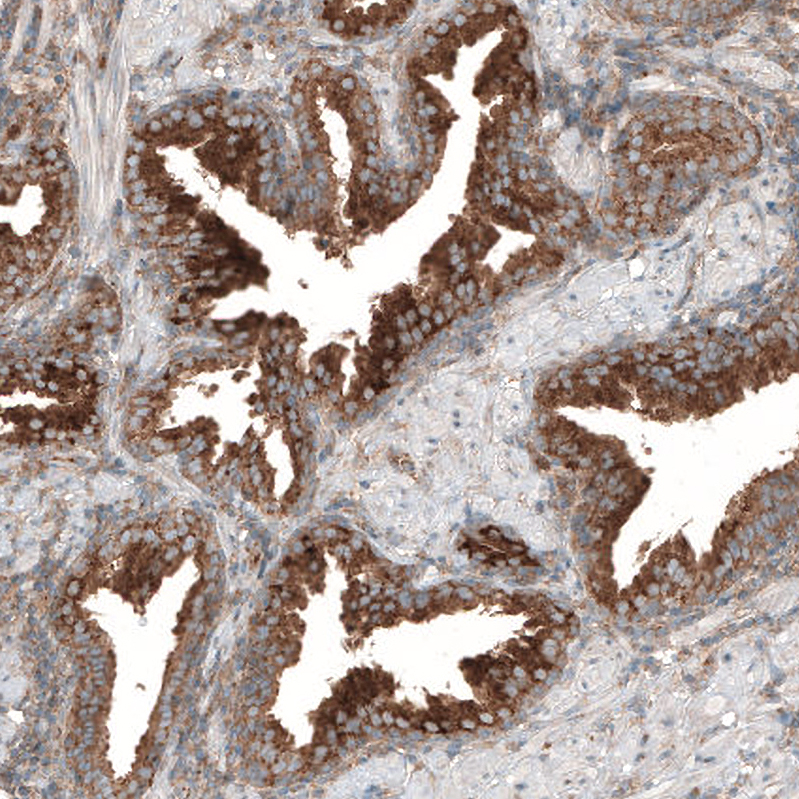

Immunohistochemical staining of human rectum shows moderate granular cytoplasmic positivity in peripheral nerve / ganglion and glandular cells.